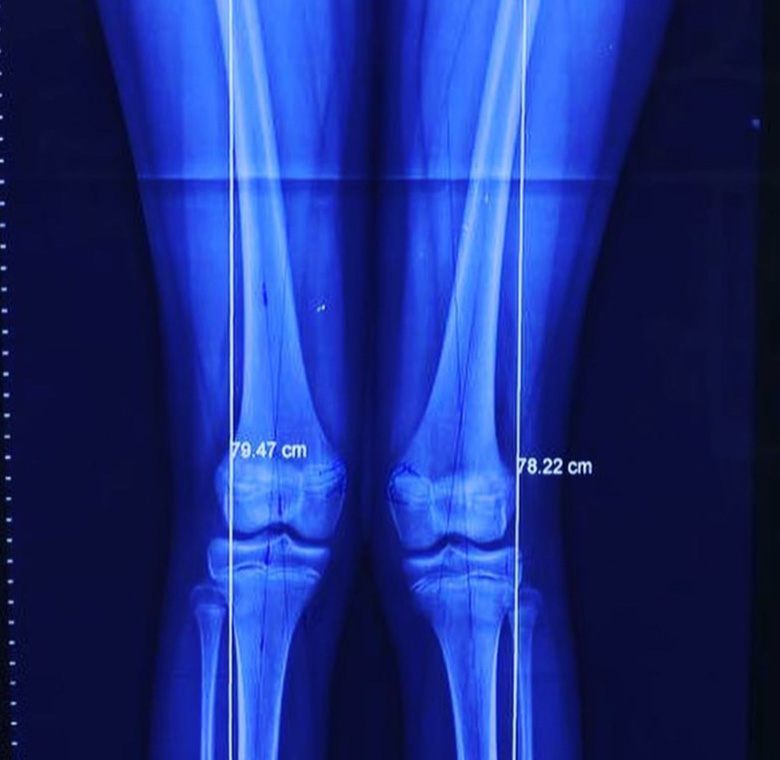

Rodillas en valgo

Deformidad rodillas en valgo

Rodillas en valgo con rótula alta